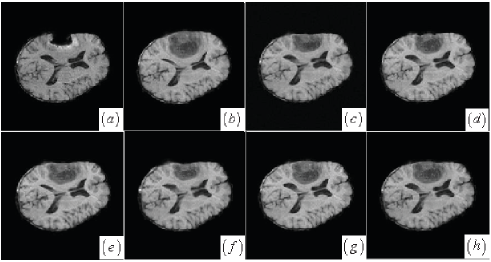

Another grayscale image registration is matching pre- and post-operative brain tumor images. Brain tissue severely suppressed by tumor in the preoperative image (Fig. 11(b)) expands after tumor resection. Tumor resection not only brings missing correspondences into the tumor region of the post-operative image (Fig. 11(a)) but also incurs local large deformations that are caused by brain shift. A successful registered result of this case should properly deform pre-operative brain tissue according to the post-operative image regardless of tumor resection. Visual inspection has revealed that the proposed, AMI, AMM and LOF methods (see Fig. 11(c)-(d),(g)) apparently perform better than the DDD and BMI methods (see Fig. 11(e)-(f)) because the local brain deformation resulted from the latter two methods is either insufficient or somewhat excessive. This visual valuation is further confirmed by validating landmark-based registration error in the following section.

The MRE and SD of the manually selected landmarks for the six methods in the three grayscale image registration are listed in Tab. 1. The proposed method for the Mickey image achieves the smallest registration error of pixels while the registration errors of AMI, DDD, BMI, AMM and LOF methods are greater than or equal to pixels. Compared with other method, the proposed method and AMI have achieved sub-pixel registration accuracy for the brain tumor resection images with the registration errors of and pixels, respectively. As for the flower image, the proposed method gets the smallest registration error of pixels, while the registration errors of other five methods are greater than or equal to pixels. In average, the proposed method maintains almost the best performance in comparison with other five methods. Although the orignial AMI method in the brain tumor resection image registration has a slight advantage over the proposed method, using cost-function masking makes AMM method worse than the proposed method in matching locally deformed structures. Simply setting the brain-tumor-region’s value to zero by cost-function masking is not enough to accurately match local salient structures with missing correspondences and local large deformations. Due to the LOF method only considering the effect of large displacments, its performance is not desired for the nonrigid registration with both missing correpondences and local large deformations.